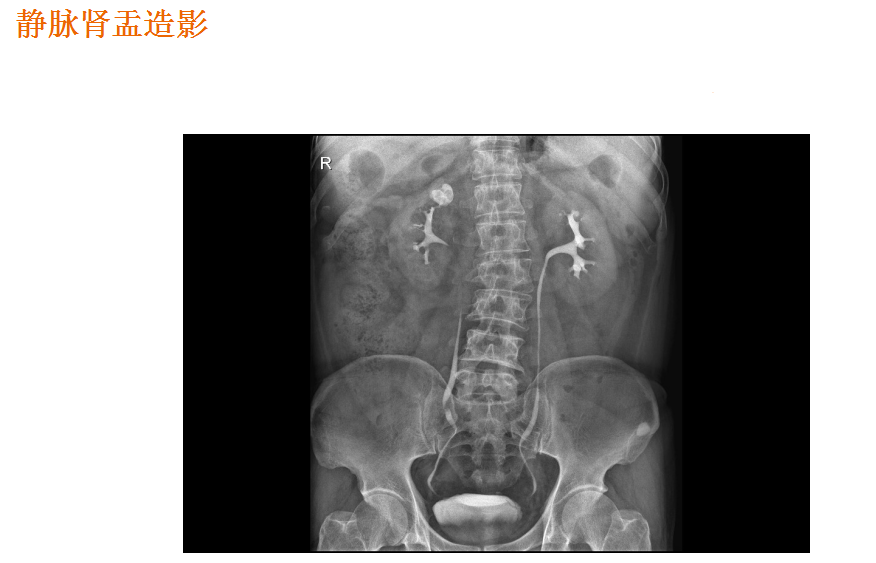

该设备属于多功能X线机,除具有传统数字胃肠机所有功能外,还有DR平板探测器X线摄影所有功能,主要用于消化道气钡双重对比造影、全脊柱拼接摄影、全下肢拼接摄影、ERCP、泌尿系造影、“T”管造影、钡剂灌肠、四肢造影、子宫输卵管造影等各类检查,是检查消化道溃疡、肿瘤、异物等疾病的主要方法之一。

在临床方面,强大的图像处理功能可以完成临床各种造影的需求。